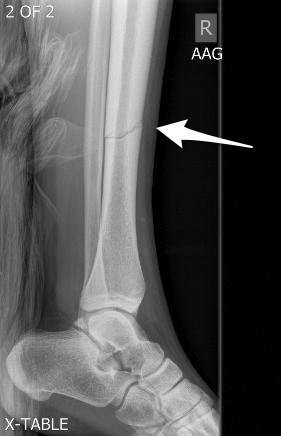

Nondisplaced fracture

It's as simple as it sounds! A fracture where the bone fragments are still in the right place, but they're... broken.

Nondisplaced fracture of the tibia

Image source